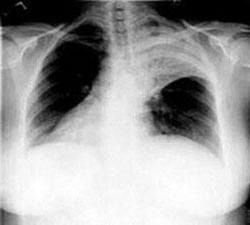

Воспаление лёгких – инфекционное заболевание, при котором поражается лёгочная ткань, альвеолы, участвующие в газообмене. Пневмонию могут спровоцировать преимущественно бактерии, но часто причиной заболевания могут быть вирусы, грибки, хламидии, легионеллы, паразиты (гельминты). Воспаление лёгких диагностируется как самостоятельная болезнь, но бывает и обострением других заболеваний. Чаще всего пневмония начинается с простуды. Симптомы очень тяжело отличить от признаков гриппа или ОРВИ:

Часто осложнением пневмонии может быть плеврит. В зависимости от тяжести заболевания и других факторов, как то: пожилой возраст, дети до года, пациенты с хроническими заболеваниями сердечно-сосудистой системы, больные помещаются на время лечения в больницу или госпиталь. Если течение болезни без осложнений и слишком высокого повышения температуры нет, то больной может лечиться амбулаторно. Во время обострения заболевания люди часто становятся источником распространения инфекции и способны заразить окружающих.

Чтобы правильно поставить диагноз доктор направит пациента на сдачу анализов, рентген. Сделает посев мокроты с целью выявления возбудителя. Потому что если пневмония вирусной этиологии то антибиотики не помогут, а только усугубят положение. С другой стороны, вирусные препараты действенны только в первые дни обнаружения симптомов, а если ситуация ухудшается, то придётся принимать антибиотики. Поэтому определение возбудителя крайне важно для правильного и эффективного лечения заболевания.